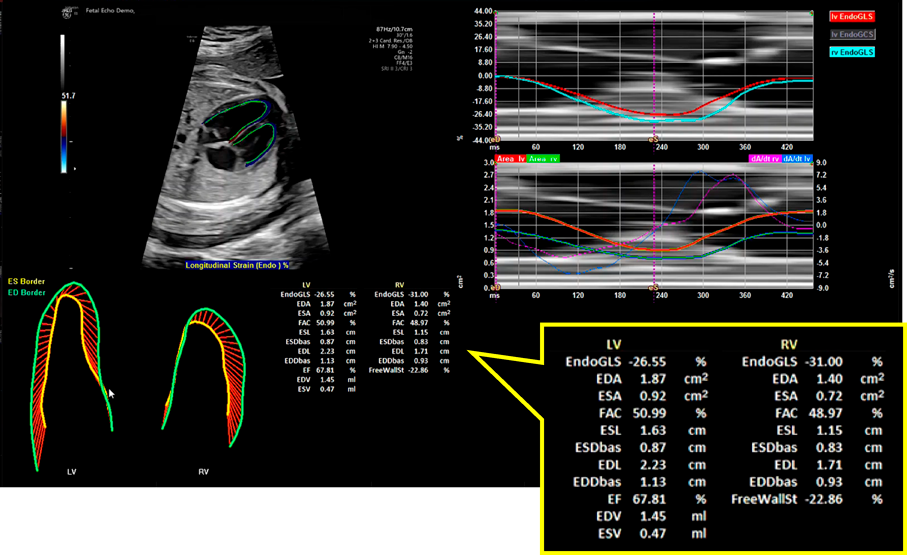

ストレインは四腔断面像もしくは短軸像の画像を記録し,それをオフラインで解析して計測する.ストレイン解析を行う際には,記録した画像の画質が良好であることに加えて,胎児心拍数は140 bpm前後と速いために画像のフレームレートが十分に高いことが重要で,フレームレートが低いとストレイン値が不正確になる可能性がある.本来は心電図を基に1心周期を判定して計測されるが,胎児では心室壁の動きから1心周期を設定して解析が行われる.現在複数のメーカーの心エコー装置で胎児のストレイン計測が可能である(Fig. 7).ただし心エコー装置・解析ソフトウェアによって解析アルゴリズムが異なるため算出されるストレイン値も異なることに注意が必要である18).これまでに各メーカーの装置により計測された胎児心室のストレイン値が多数報告されているが,値や在胎週数による変化は報告により一定しない.本邦からも多施設共同研究による多数例の日本人正常胎児のストレイン値が報告されており,左室,右室のGlobal Longitudinal Strain; GLS(心室全体の長軸方向ストレイン)はそれぞれ−24.3±3.5%,−23.5±3.7%で,在胎週数が進むにつれて増加(絶対値は低下)するとされている19)

Pediatric Cardiology and Cardiac Surgery 41(1): 11-19 (2025)

Fig. 7 Speckle tracking法を用いた胎児左室・右室のストレイン解析結果画面

データを拡大して示す.